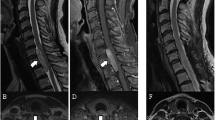

This study retrospectively analyzed 60 consecutive patients who underwent posterior surgical resection for thoracic IDEM meningiomas at a single institution between 2007 and 2022. Patients were stratified into two groups according to tumor location on preoperative MRI: Ventral group (n = 23) and Dorsal/Lateral group (n = 37). Clinical outcomes were assessed using the modified McCormick scale (MMCS). Surgical parameters and complications were also compared.

Patients in the Ventral group had significantly larger sagittal tumor diameters and higher spinal canal occupancy rates than those in the Dorsal/Lateral group (p < 0.05). Preoperative motor deficits were more frequent in the Ventral group (86.9 vs. 51.3%, p < 0.01). Estimated blood loss was greater in the Ventral group (p = 0.01). Intraoperative motor evoked potential deterioration occurred more often (p = 0.04). Although both groups showed neurological improvement postoperatively, the percentage of patients reaching MMCS Grade I at final follow-up was significantly lower in the Ventral group (17.3 vs. 54.0%, p < 0.01). No tumor recurrence was observed in either group during the follow-up period (mean: 61.4 months).